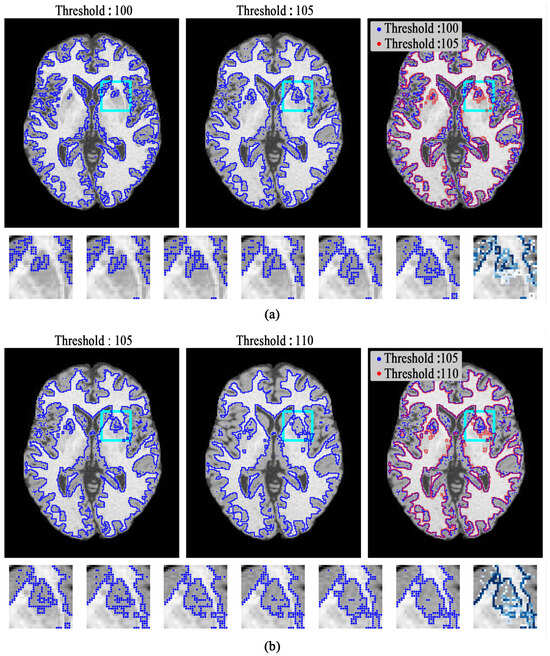

In Figure 3, we can see that the boundary in the bottom right around the white matter stays stable when threshold changes from 100 to 105, but those around the gray matter (GM, shown in the cyan bounding box) change significantly. Furthermore, when the threshold changes from 105 to 110, the boundaries inside the GM change significantly. Both the situations show that those boundaries near the truth of tissue boundaries may possess higher stability as the thresholds change.

Figure 3.

Edges of the thresholding result. (a) Top left: 100; top middle: 105; top right: 100 (blue), 105 (red); bottom: local thresholding result of the region in the cyan box with 100–105 and the heatmap at the rightmost; (b) top left: 105; top middle: 110; top right: 105 (blue), 110 (red); bottom: local thresholding result of the region in cyan box with 105–110 and the heatmap at the rightmost. (The heatmap was generated as follows: As the threshold varies, superimpose the boundary pixels and increase the pixel count by one each time. The pixel with the highest count is set to the darkest blue. Thus, the darker a boundary pixel is, the more stable it is).

To the best of our knowledge, there are few intensity-based methods that consider pixel-wise edge stability. Li [56] evaluated shape stability with the region expanding rate (RER) and selected a threshold with a low RER; Serena [57] considered the area-stable elongation to find the stable region. All of the above methods measured an overall stability pattern between boundaries. In fact, pixels on the edge possess different stability values, as Figure 3 shows. Therefore, we can conclude that pixels on the edge possess stronger stability.